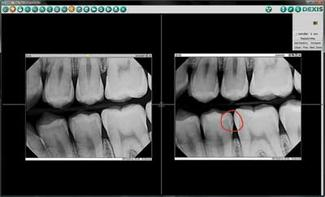

Digital imaging is a valuable educational tool, because images appear almost instantly on the screen. With a click of my computer mouse, I can compare side–by–side the patient's older and newer images.

I always say, “Seeing is believing,” and digital technology raises my diagnostic capabilities and treatment planning to a higher level.

When I can sit beside a patient and with the click of a mouse point out on the monitor the exact spots where the decay has gotten deeper, the patient is more likely to accept treatment.

Even better, the sharp contrast delivered when I enhance images with my DEXIS ClearVu™ allows the patients to see their issues as clearly as I can. Patients appreciate their shorter appointments as well as the reduced radiation of digital imaging over traditional methods. I can easily and quickly e–mail digital X–rays to my colleagues for consultation. Financially strapped patients appreciate the fact that your technology avoids scheduling an unnecessary trip to a specialist.